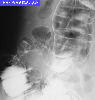

A case of mesenteric panniculitis that induced multiple stenosis of the large intestine.

X-ray